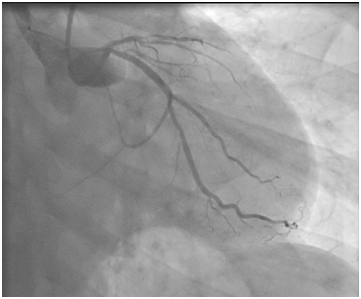

The second case

A 59-year old male, smoker, was admitted for anterior AMI with a cardiogenic shock in 2002. A primary PCI was done. In the angiogram, there was an acute thrombotic occlusion of the first segment of the LAD. A direct stenting of the culprit lesion was done successfully with a BMS (3.5/9mm; Synchro; SORIN®; Costa Mesa, California). No post-dilatation was done. Afterwards, he was discharged on ASA (100 mg once daily) and ticlopidine (500mg once daily for one month). Eleven years later, he was admitted again for chest pain due to an anterior AMI. Emergency coronary angiography revealed a total thrombotic occlusion of the stent of the LAD. On the IC stent®, there wasn’t an underdeployment. A predilatation with a balloon 2.5x15mm restored a TIMI III flow, then optimized by a non compliant balloon dilatation 3x8mm with an excellent angiographic result. He was discharged with DAPT (clopidogrel 75mg + ASA 100mg) for 3months then 100mg ASA daily alone long life. He was seen 3months later, free of any symptoms (Figure 4-6).

Figure 4 Thrombotic occlusion of the proximal LAD.